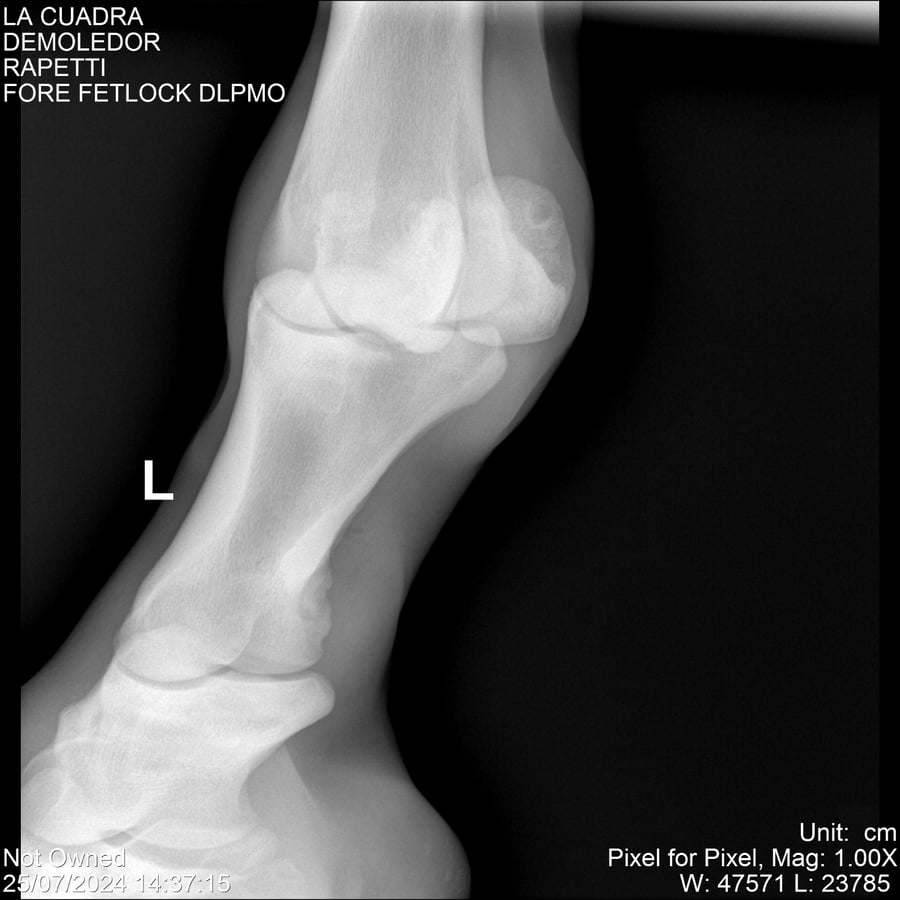

LOTE 14, DEMOLEDOR 🔥 🔥 🔥 Lote Anterior Volver al remate Lote Siguiente Ficha Contacto Montevideo - Ficha del Lote Identificador: #284454 Categoría: Yeguarizos Montevideo - 89 Visualizaciones ClicData Contacto Empresa: Abelenda N. R., Walter Hugo Nombre*: Teléfono* : E-mail* : Mensaje Enviar Registrese gratis Este contenido Exclusivo está disponible sólo para usuarios registrados Ingresar